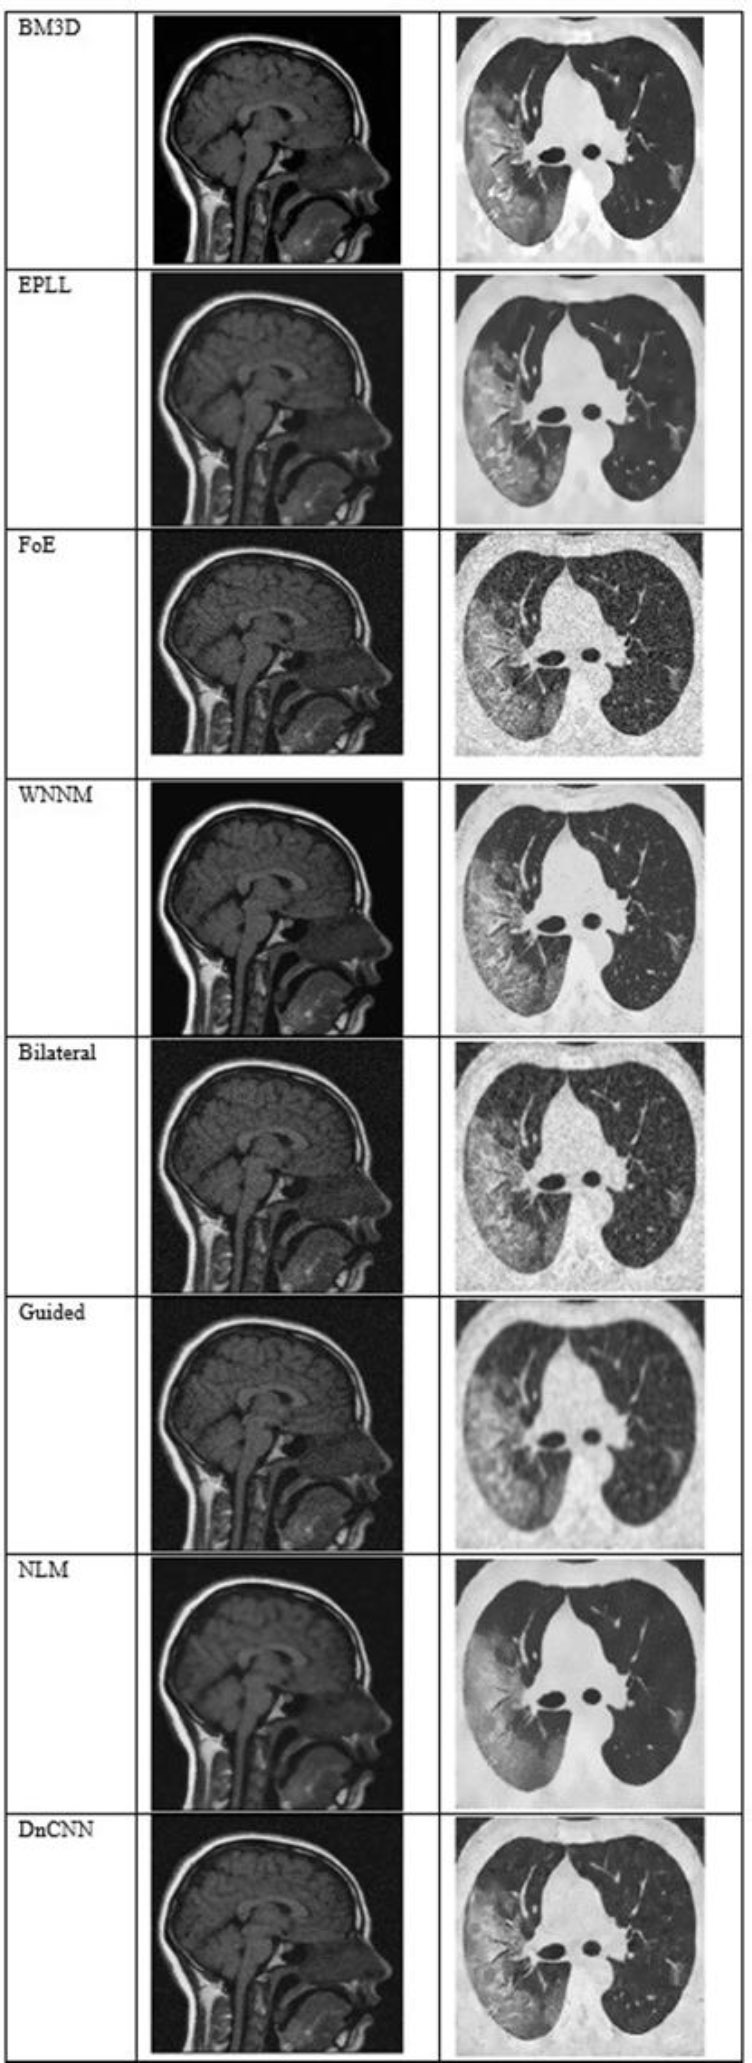

Fig. (5) shows the results at a noise variance of 0.05, where it has been observed that the BM3D, EPLL, and WNNM algorithms produce clearer images compared to other algorithms. NLM and DnCNN also perform well, but not as well as the above-mentioned three algorithms.

The output of different algorithms at a noise variance of 0.05.

Fig. (6) shows the results at a noise variance of 0.09, where it is observed that the BM3D, EPLL, and WNNM algorithms produce clearer images compared to other algorithms. Another algorithm, DnCNN, also performs well, but not so well as the above-mentioned three algorithms.

The output of different algorithms at noise variance 0.09.